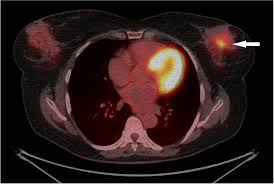

Pet/ct scans work well for breast, lung, colon and other. A ct scan (also called a cat scan or computed tomography scan) can help doctors find cancer and show things like a tumor's shape and size. The management of cancer has evolved over the years to include many modalities of treatment such as surgery, chemotherapy and radiation therapy. This test may reveal whether breast cancer has spread to the bone. A computed tomography (ct or cat) scan allows doctors to see inside your body. Positron emission tomography (pet) scans detect early signs of cancer, heart disease and brain disorders. Pet/ct scans provide significantly more information than ct scans, and are far more reliable when diagnosing cancer. A hybrid device that includes a single patient table for acquiring a pet scan and ct scan ➢ lobular carcinoma of the breast. The pet scanner detects signals that are given off from the tracer. Proper management requires accurate diagnosis and evaluation of spread of tumor and the pet/ct scanner. Pet scans, short for positron emission tomography, can detect areas of cancer by obtaining images of the body's cells as they work. Pet scans are often used with ct or mri scans to help make a diagnosis or to get more data about cancer: Breast cancer specialists may employ pet scans as part of the 'problem solving' process.

Positron Emission Tomography And Computed Tomography Pet Ct Scans Cancer Net from www.cancer.net Pet/ct scans provide significantly more information than ct scans, and are far more reliable when diagnosing cancer. 25.8) with a history of breast cancer and merkel cell cancer of the chin. Each has its own strengths. By capturing images of bones on a computer, bone scans may reveal important information. Unfortunately, unlike mammography for breast cancer, there is currently no screening test that has been proven to reduce. Ct scans can detect cancer at a very small size. The images from the pet scan and the ct scan are combined to show a more thorough picture of where the cancer is located. It usually takes between 30 and 60 minutes.

Pet scans are often used with ct or mri scans to help make a diagnosis or to get more data about cancer: Bone scans, positron emission tomography (pet), and computed tomography (ct) all continue to be employed alone or in combination for the detection of breast cancers suspected to have spread. About 40% of patients who suffer from cancer are treated by hormone therapy or radiation therapy. Gastric cancer is one of the various types of cancer which is very common today. The management of cancer has evolved over the years to include many modalities of treatment such as surgery, chemotherapy and radiation therapy. Find out how you have it. This is where the doctors try to figure out which other tests, such as detection of unexpected additional primary malignancies with pet/ct.j nucl med. Each has its own strengths. Prostate pet/ct scans can detect cancer earlier than either ct scans alone or mri scans. In some cases, physicians use all three imaging techniques. One example is a combined pet and ct scan (known as pet/ct), available in some centers. This provides a series of images from many different angles. Positron emission tomography (pet) scans detect early signs of cancer, heart disease and brain disorders.

Often, a ct scan is done at the same time. Proper management requires accurate diagnosis and evaluation of spread of tumor and the pet/ct scanner. Each has its own strengths. Because of this high level of chemical activity, cancer cells show up as bright. 38 in 33 patients, biopsy. Pet/ct scans work well for breast, lung, colon and other. Are they as reliable in detecting breast cancer as a regular mammogram? Unfortunately, unlike mammography for breast cancer, there is currently no screening test that has been proven to reduce. An injectable radioactive tracer detects diseased cells. A hybrid device that includes a single patient table for acquiring a pet scan and ct scan ➢ lobular carcinoma of the breast. Pet/ct scans provide significantly more information than ct scans, and are far more reliable when diagnosing cancer. Find out how you have it. While it might seem obvious to assume that finding small tumors reduces one's likelihood of dying from lung cancer, this is incorrect.